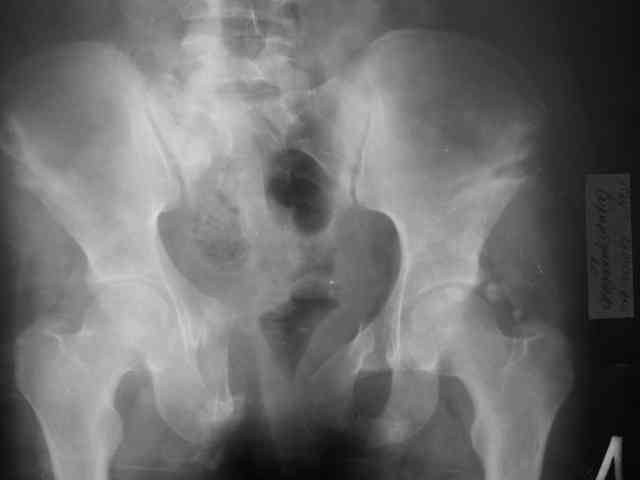

Уважаемый Алексей Владимирович и коллеги! Предоставляю Вашему вниманию неотдаленный результат лечения (5 месяцев) 20 летней девушки с переломом костей таза. Начало - http://weborto.net/forum/1143448738/index_html Укорочение левой нижней конечности 2 см. Снимки в 2 проекциях прилагаются. По ссылке на rapidshare можно скачать видео c функциональным результатом, ~11мб, ссылка будет работать 30 дней. Комментарии приветствуются. -- Best regards, Коваленко

Боли в покое отсутствуют, возникают при длительной ходьбе более 1.5км и длительном сидении. Половой жизнью пока не живет(до травмы тоже не жила). Как стоит-ходит - в видеоматериале.